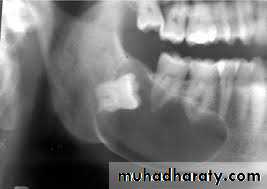

11- Root fragment (Retained Root ) :